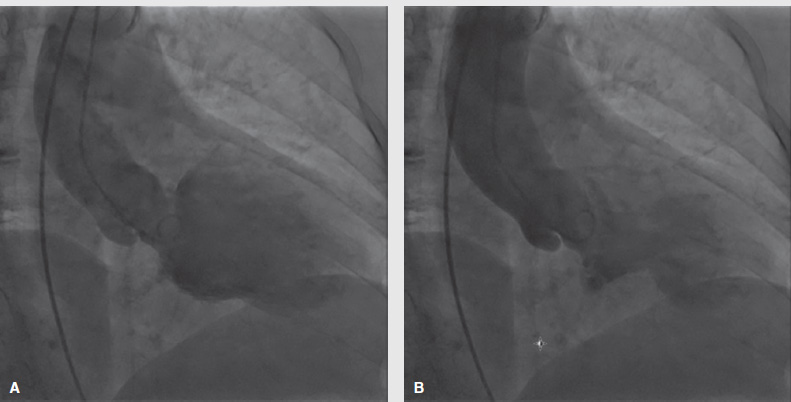

Her past medical history was significant for hypertension, asthma, and hypothyroidism. Due to persistent chest pain unrelieved by morphine, aspirin, and sublingual nitroglycerin, she underwent coronary angiography. No significant coronary stenosis or calcification was noted during the angiography. The ventriculogram revealed a hypokinetic left ventricle with apical ballooning (Figure). A transthoracic echocardiography revealed a normal ejection fraction at 50-54%. She was diagnosed with takotsubo cardiomyopathy with normal ejection fraction. After the procedure, we learned that the patient had been under a tremendous amount of stress due to her home burning down in a fire one week prior to presentation. She did not return to clinic for follow-up.

Figure. Left ventricle during diastole (A) and systole (B) with apical ballooning.